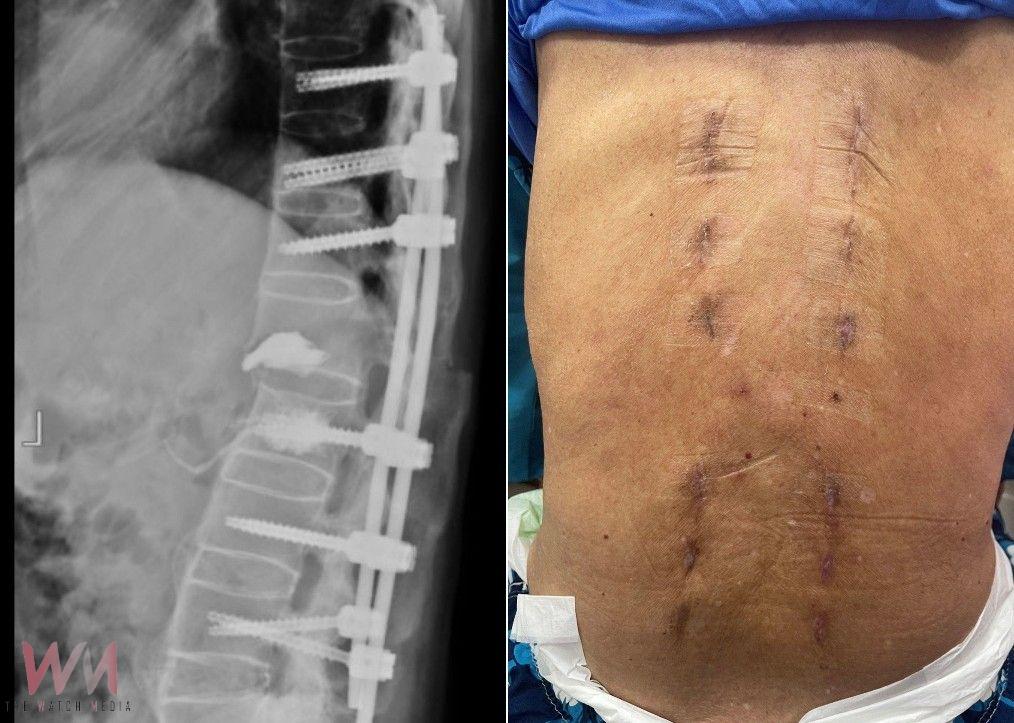

幸運的是,張先生並未出現神經壓迫症狀,下肢肌肉力量與知覺皆正常。考量到脊椎不穩定的危險性,喻醫師迅速幫張先生安排從胸椎第十節到腰椎第四節的微創脊椎固定手術。相較傳統手術,微創手術僅需在脊椎釘入口處開小傷口,最大程度保留肌肉及周邊組織。此外,手術中也搭配了電腦斷層導航系統,提高手術精準度及縮短手術時間,不僅能大幅減輕術後疼痛,也讓患者恢復速度更快。